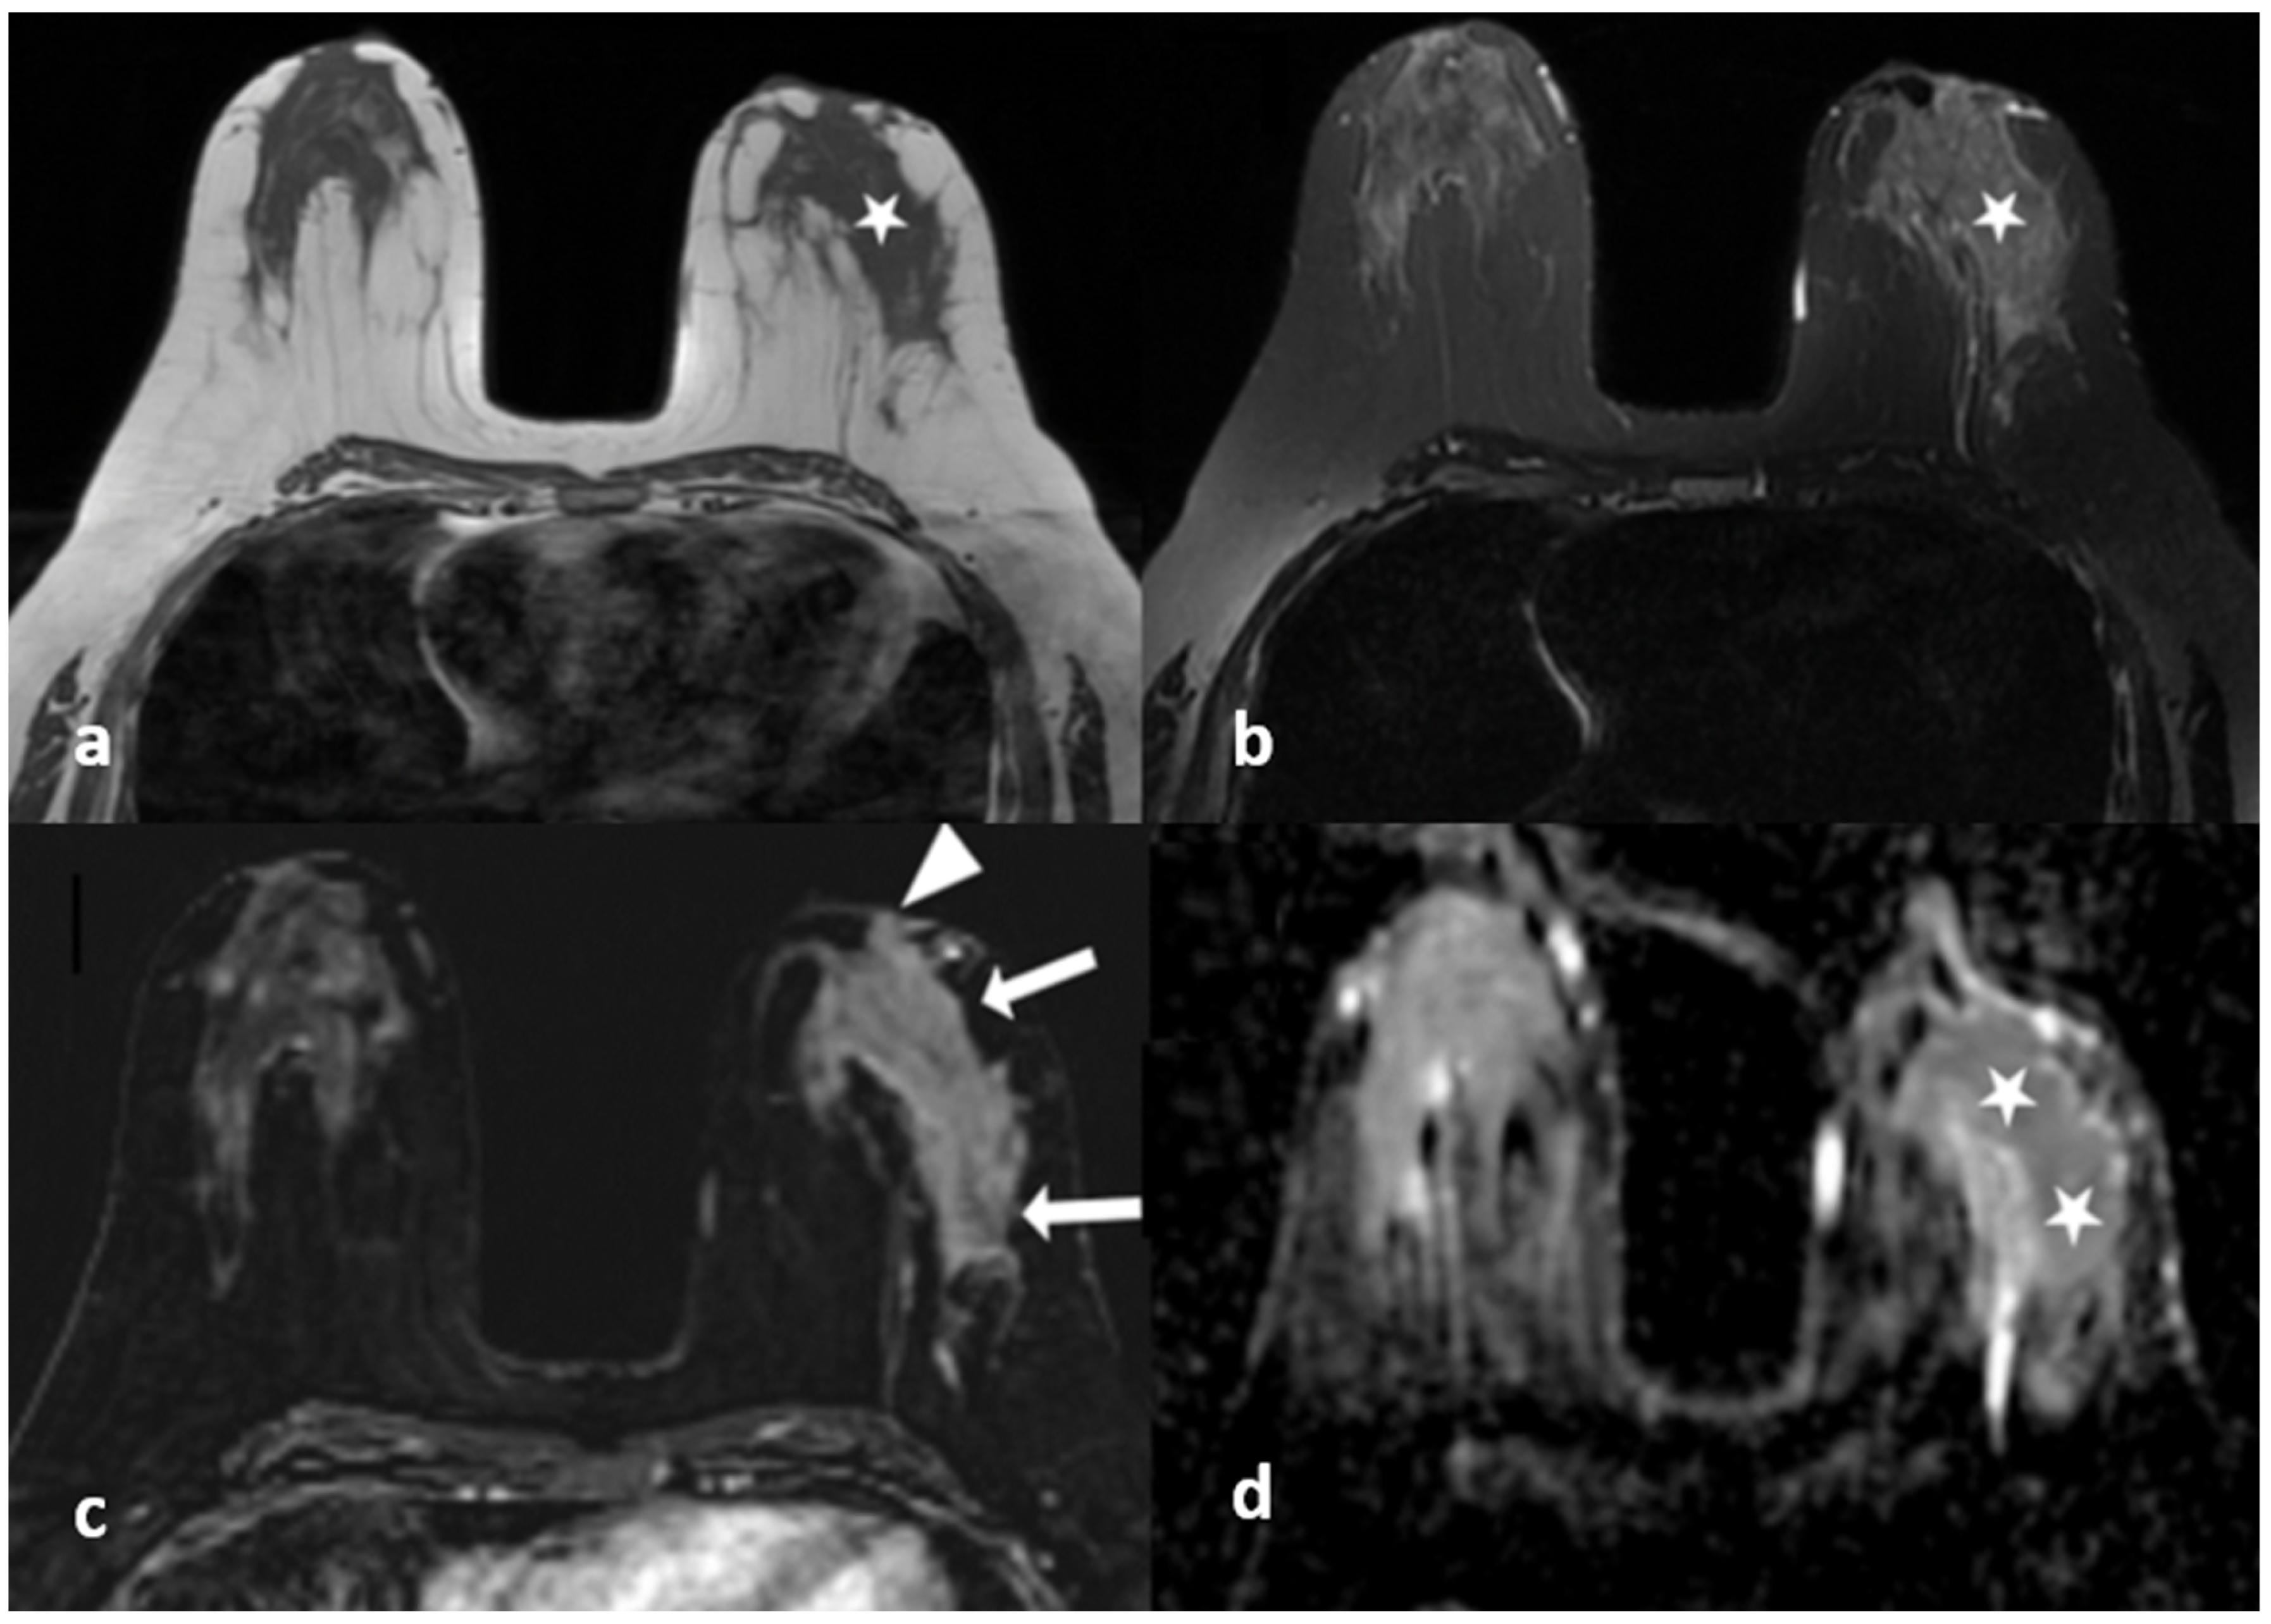

3.1. Non-Enhanced Images

3.2. Contrast-Enhanced Images

3.3. Overall Evaluation